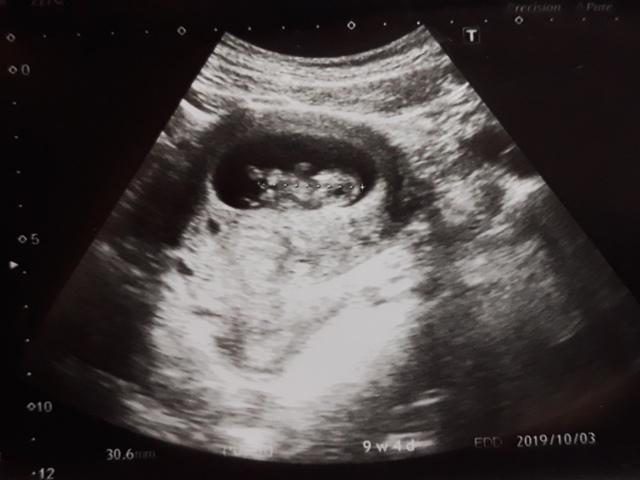

當小純進入診間看診時,我並沒有進去,因為小純說,有時男生不能進去,會被請出來。在外頭等待的我感到很緊張,不久之後,謢理人員請我進入診間,我嚇了一跳,想說發生什麼事了,進入之後,得知小純真的懷孕了,而且已懷了九星期又五天。看診的醫師說,驗孕棒第二條線淡淡的,沒想到胚胎照出來那麼大了,說Baby很健康。還說一閃一閃的是他的心跳,有頭、有手、有腳還有臍帶。小純後來說看了內心覺得很感動,才叫我一起進去看。

小純肚子裡的Baby超音波圖↓